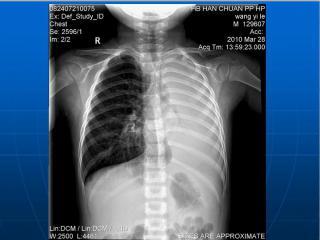

肺不张诊断及鉴别ppt课件下载